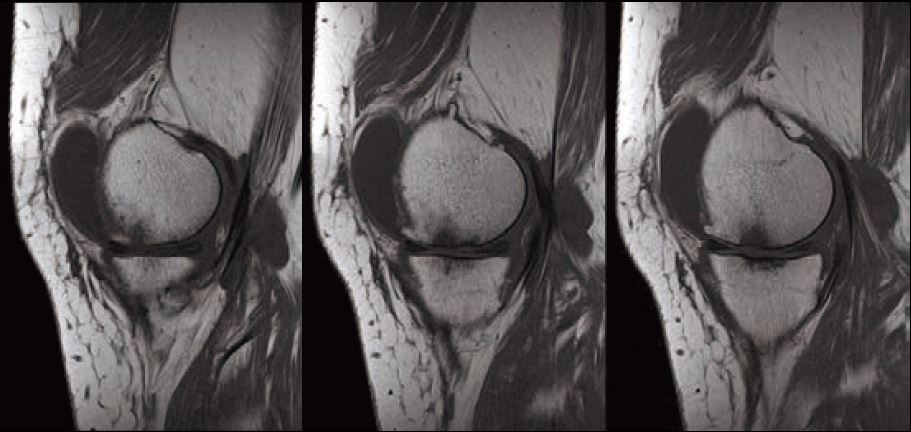

Випадок 2. Коліно високої роздільної здатності

Чоловік 26 років проходить посттравматичну діагностику, є скарга на біль.

• Відсутність травматичного пошкодження.

Рис. 5 Sg FSE T2 FS і Sg FSE T1, товщина зрізу 3 мм, роздільна здатність 0,2 мм.

Рис. 6 Sg косий FSE T2, товщина зрізу 2 мм, роздільна здатність 0,2 мм.

Рис. 7 Co FSE PD FS, товщина зрізу 3 мм,

роздільна здатність 0,2 мм.